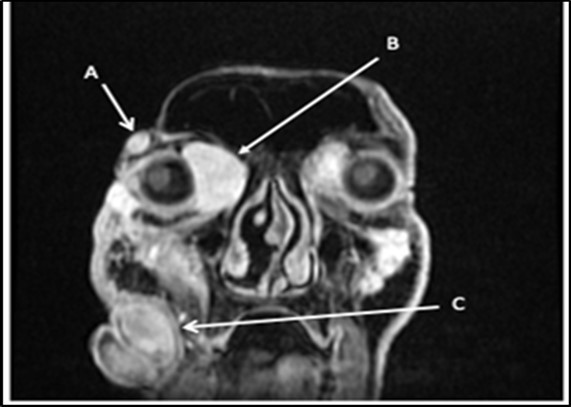

With the previous biopsy done 5 months ago, the primary working impression is neurofibromatosis. These types of lesions tend to be painless, slowly growing, solitary, skin-colored, soft, flaccid, rubbery to firm papules or nodules with a smooth surface measuring up to 2 cm. Classic characteristics include a “bag-of-worms” consistency and eyelid involvement producing an S-shaped deformity in cases of the plexiform variants1. The lesion also invaginates with pressure. The prevailing diagnostic criteria of Figure 2. Multiple facial lesions are radiologically consistent with neurofibromas. (A) 1.8x0.9x1.7cm right lateral temporal mass (B) 3.2x3.3x4.5cm right medial intraorbital mass (C) 8.6x7.3x6.0cm right nasal mass neurofibromatosis type 1 are met if 2 or more of the following are present: (1) ≥ 6 café au lait patches (2) ≥ 2 neurofibromas of any type, or 1 plexiform neurofibroma (3) axillary or inguinal freckling (4) ≥ 2 lisch nodules, (5) optic glioma, (6) sphenoid dysplasia or thinning of long bone cortex with or without pseudoarthrosis (7) first-degree relative diagnosed with neurofibromatosis type12. In contrast to this, our patient did not satisfy any clinical manifestations of Neurofibromatosis type 1. The closest differential of neurofibroma would be a schwannoma. If present on the orbit, they are insidious and proptose gradually without pulsations. Most tumors infiltrate the superior quadrant, causing inferiorly displaced proptosis or frank hypoglobus3. Patients may experience diplopia, eye movement limitation, diminished visual acuity, and optic nerve compression symptoms, including scotomas dyschromatopsia, and impaired contrast sensitivity. They may also experience pain or paresthesia in the distribution of the nerve. In severe cases, there may be a palpable orbital mass4. Only one case has been reported of a bilateral orbit involvement5. Another differential would be the malignant transformation of neurofibroma. Malignant peripheral nerve sheath tumor may arise from a preexisting nerve sheath tumor in neurofibromatosis type 1 and can arise in virtually any anatomic location. The most common sites are the trunk and extremities, followed by the head and neck. There is no gender preference, and it tends to occur in younger individuals with Neurofibromatosis1. Histologic evaluation is necessary but not always specific and requires correlation with clinical and radiologic findings6. At this point, the clinical presentation is consistent with the previous histopathologic diagnoses, that of a neurofibroma. Although a neurofibrosarcoma would also have a similar presentation at its early stages, its predilection for arising from NF type 1 lesions is not seen in our patient.

Figure 2.Multiple facial lesions radiologically consistent with neurofibromas. (A) 1.8X0.9X1.7cm right lateral temporal mass (B) 3.2X3X4.5 cmright medial intraorbital mass (B) (C) 8.6X7.3X6.0 cmr right nasal mass

Multiple facial lesions radiologically consistent with neurofibromas. (A) 1.8X0.9X1.7cm right lateral temporal mass (B) 3.2X3X4.5 cmright medial intraorbital mass (B) (C) 8.6X7.3X6.0 cmr right nasal mass